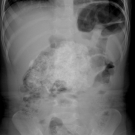

Radiology Quiz

05/04/2025

Ankuriti Singla, MBBS; Ananya Singla; Roli Agrawal, MD

A previously healthy 2-year-old girl presented to the pediatrician’s office with chief complaint of abdominal discomfort.